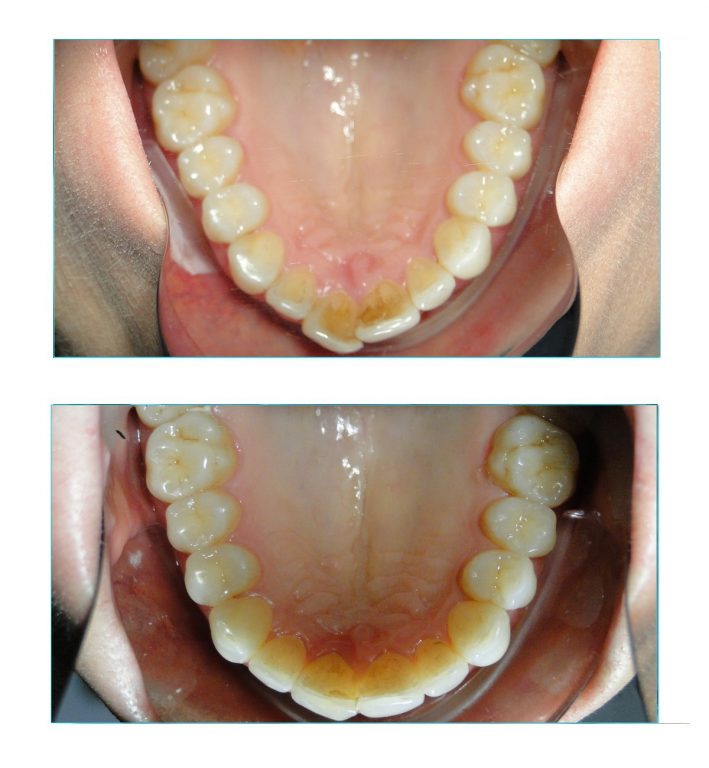

Expansão e alinhamento com aparelho lingual foi a solução usada para corrigir o estreitamento das arcadas nessa paciente.

Além da compressão maxilar, ela também apresentava mordida cruzada no lado esquerdo e um severo apinhamento em ambas arcadas.

Para melhor acomodação dos dentes, foram realizados desgastes interproximais nos dentes anteriores superiores e inferiores. Como sempre, os desgastes são imperceptíveis quando bem realizados.